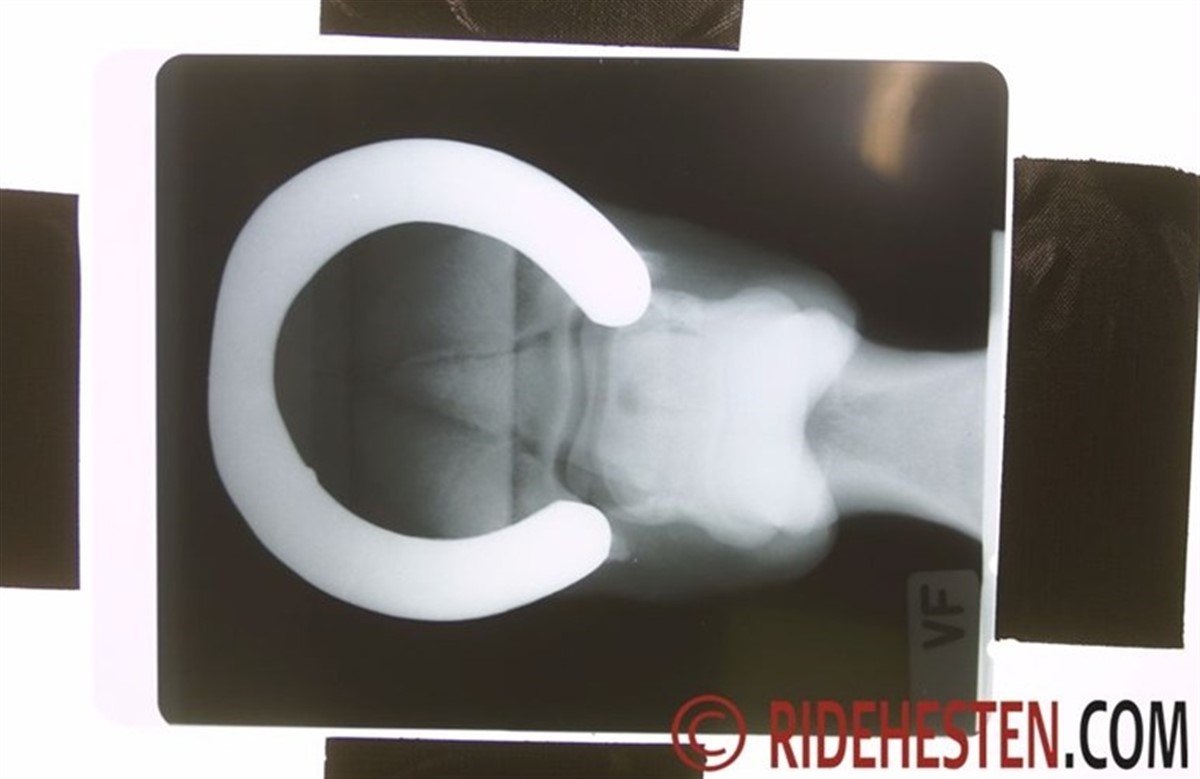

Røntgen giver bl.a. mulighed for, at dyrlægen kan vurdere forholdet mellem hovbenet og hovvæggen og I samarbejde med smeden finde frem til en optimal pleje af hoven. Dertil kan faktorer som sålens dybde, vinkler, balance og generel sundhed også vurderes mere dybdegående vha. røntgen. Hoven er dog ikke en statisk form, men ændrer sig i perioden mellem beskæringer, hvor forlængelsen af tåen ændrer vinklerne og presset på senerne. Røntgen kan også vise, om hoven har diverse indre skader. Forskere anbefaler, at men benytter røntgen af hoven, ved fx anormal hovvækst, halthed eller lignende. Det er vigtigt med røntgenbilleder af en god kvalitet, for at de I tilstrækkelig grad kan hjælpe til en optimal hovpleje. Kilde: The Horse